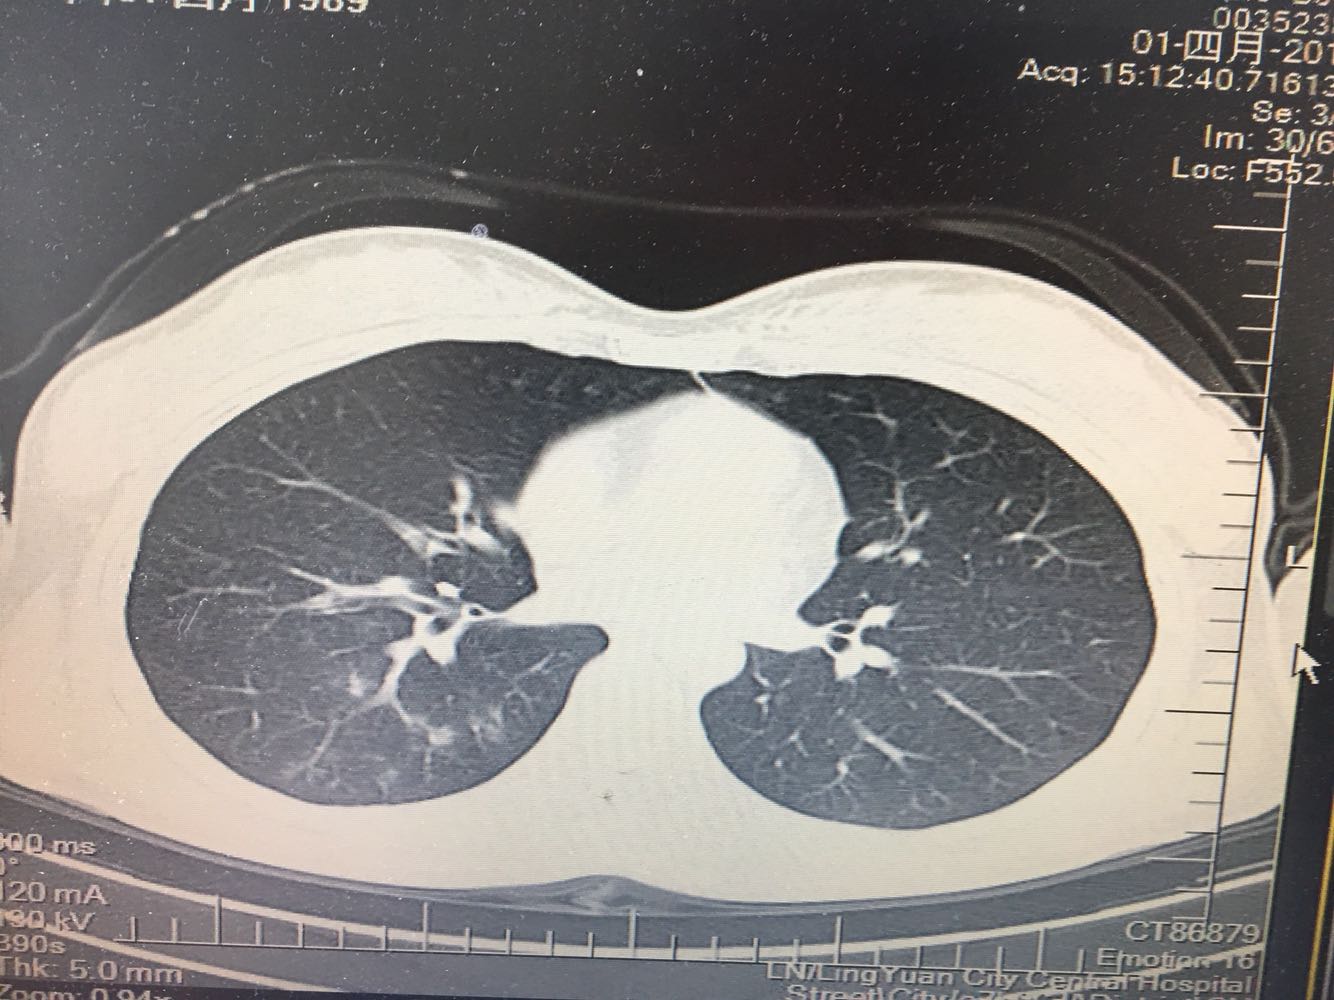

女,26岁,咳嗽1周,咳痰不畅,咽喉痒,口服阿莫西林无好转,昨日发热,体温38.5摄氏度,于门诊查肺CT后以肺炎收入院,病来无盗汗,无咳血,无消瘦及乏力,无头痛,无肢体酸痛,饮食睡眠可,二便正常

神清言明,咽部无充血,扁桃体不大,双肺呼吸音清,无罗音,服软无压痛。

支原体肺炎?肺结核?

支原体抗体1:160,结核抗体弱阳性。支原体肺炎个别可见上叶病变,该患无结核中毒症状,考虑支原体肺炎可能性大,但肺尖为结核好发部位,需要抗炎治疗后复查观察疗效。